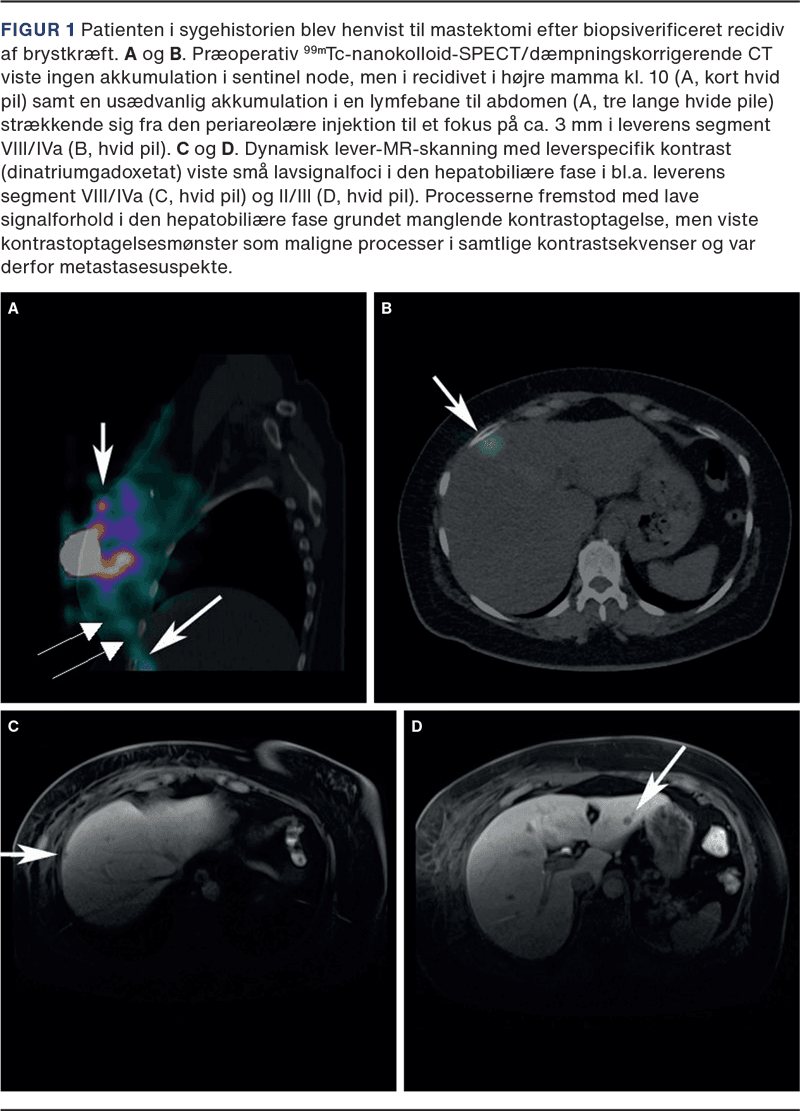

Præoperativ SN-LS med SPECT/dæmpningskorrigerende CT visualiserede ingen SN i aksillerne, mammariagebetet, subpektoralt eller periklavikulært, men aktivitet i en bane lateralt for og parallelt med m. rectus abdominis dxt. strækkende sig fra brystet til et fokus på 3 mm i leverens segment VIII/IVa (Figur 1). Den abnorme drænage rejste mistanke om leverinvolvering. Den efterfølgende MR-skanning viste tre metastasesuspekte foci i henholdsvis leverens segment VIII/IVa, VI og II/III, hvilket blev bekræftet ved UL-vejledt biopsi, som viste IDC med samme receptorprofil som primærtumoren og recidivet.